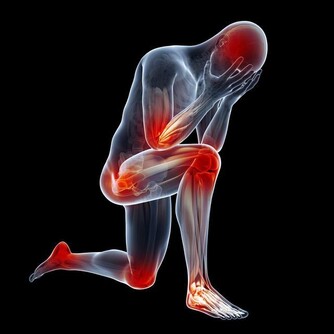

高尿酸是一種生活方式的疾病,想要降尿酸,不管是吃藥治療,還是飲食上的調整,都要牢記2個原則:減少尿酸生成,促進尿酸排泄。

減少尿酸的生成,在生活中主要體現在飲食的調整上,不單單要限制高嘌呤食物的攝入,比如少吃或者不吃海鮮、動物的內臟,少和白酒啤酒等,還要少吃高糖、高脂肪的食物。因為血樣、血脂和血尿酸之間具有相互促進的作用。

除此之外,要多運動,控制自己的體重。因為減肥和運動也是有利於降尿酸的行為。但是需要提醒大家的是,減肥需要循序漸進,切莫心急。而運動也要選擇適合自己的運動項目,根據自己的身體情況來選擇,避免運動強度過大,造成不必要的身體傷害。